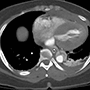

A 49-year-old woman with a history of hypertension and smoking presented to an outside hospital with sudden onset chest pain and hypotension. Computed Tomography/ Angiography (CTA) of the chest and abdomen revealed a type A aortic dissection extending from the ascending aorta to the left common iliac artery. (Figure 1) Of note, there was a significant pericardial effusion and left pleural effusion. Due to her hypotension and tamponade physiology, the patient was rapidly intubated followed by unsuccessful pericardiocentesis. The patient was then transferred to our institution for emergent dissection repair.

Figure 1a-e. Computed Tomography/Angiography (CTA) at

presentation demonstrating a type A aortic dissection.

Figure 1a. Axial CT at level of the pulmonary artery. The false lumen in the ascending aorta (white arrow) has minimal flow.